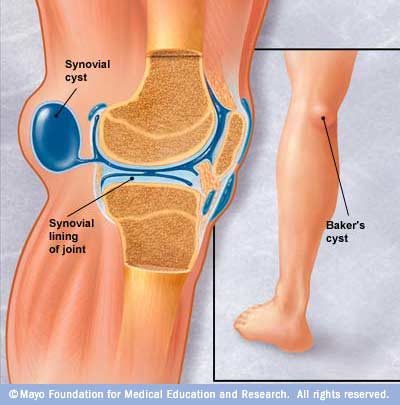

A Baker's cyst is usually the result of a problem with your knee joint, such as arthritis or a cartilage tear. Both conditions can cause your knee to produce too much fluid, which can lead to a Baker's cyst.

Image courtesy - tabletsmanual.com

It is very important to know that the Bakers Cyst is an effect of an underlying Condition. It is not the primary problem. So getting the cyst drained or removed without treating the underlying condition will just cause the Cyst to reappear.

Although a Baker's cyst may cause swelling and make you uncomfortable, treating the probable underlying problem usually provides relief.